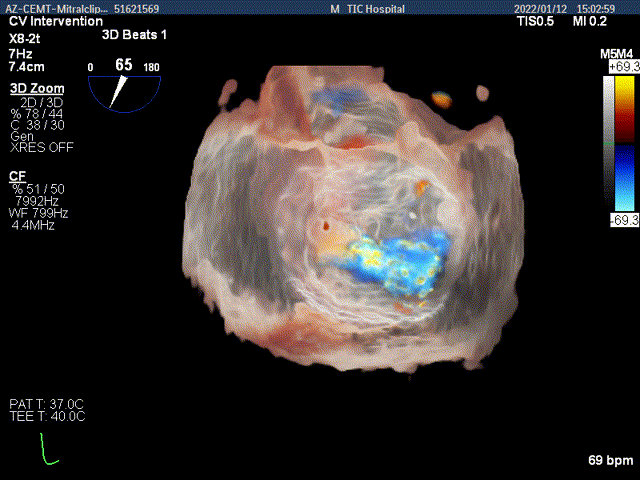

3D MV View:二尖瓣AC区为主(累及部分1区)脱垂并腱索断裂

3D-color MV view:大量返流,主要来源于AC区

3D-color-VIEW验证残余返流来源

3D-Color-view验证微少量残余返流